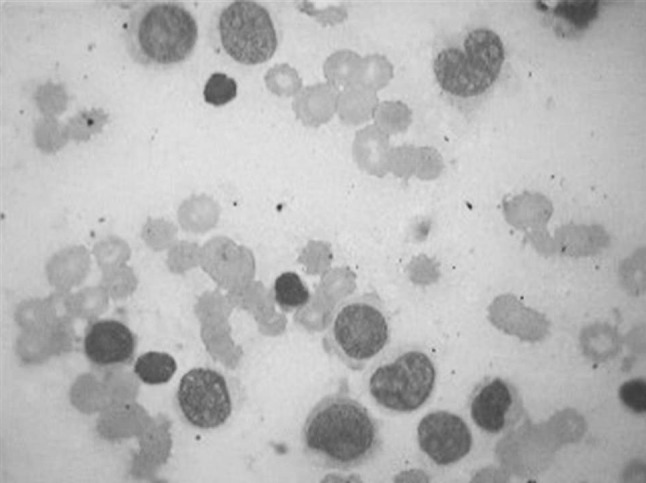

A 7 month old male infant presented with fever and breathlessness. On examination, child had pallor. Hemogram revealed hemoglobin of 4.6 g/dL, TLC 1.64 lacs/cu mm, platelet counts of 90,000 per cu mm with 90 % blasts, having high nucleo cytoplasmic ratios, vesicular chromatin and prominent nucleoli (Fig. 1). A provisional diagnosis of acute leukemia was made with differentials of infantile acute lymphoblastic leukemia/acute myeloid leukemia (AML)/mixed phenotype acute leukemia.

Fig. 1.

Peripheral smear showing blasts with high N/C ratios, vesicular chromatin and prominent nucleoli (Giemsa, 100×)